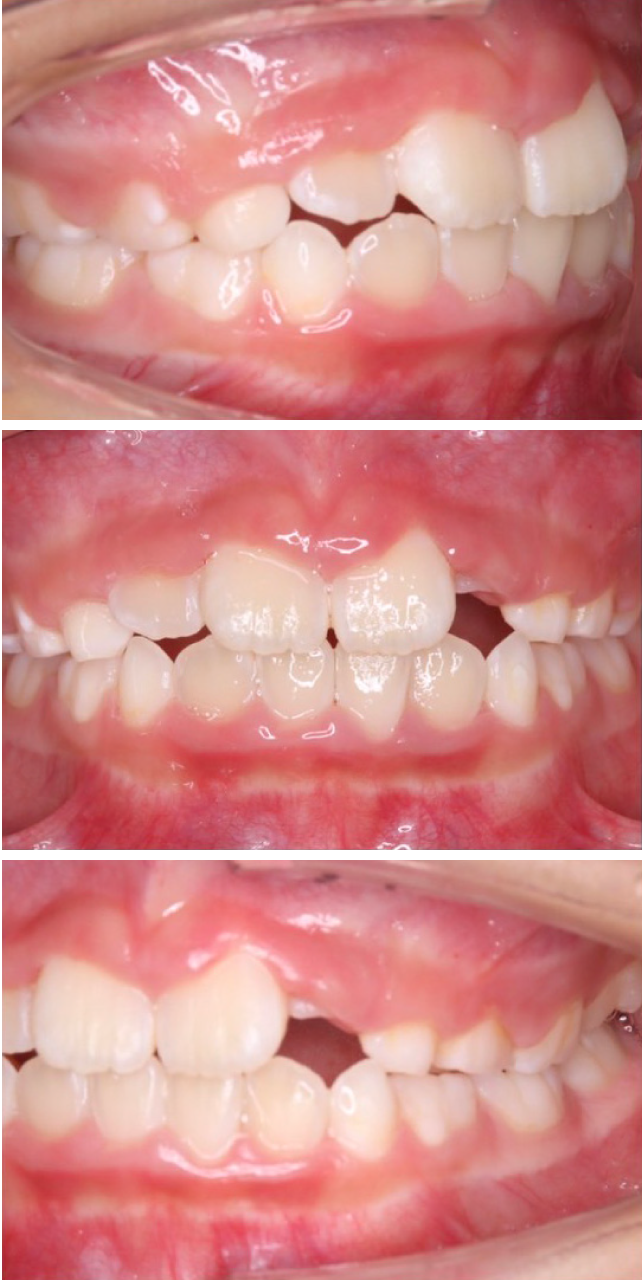

当院の症例

CASE